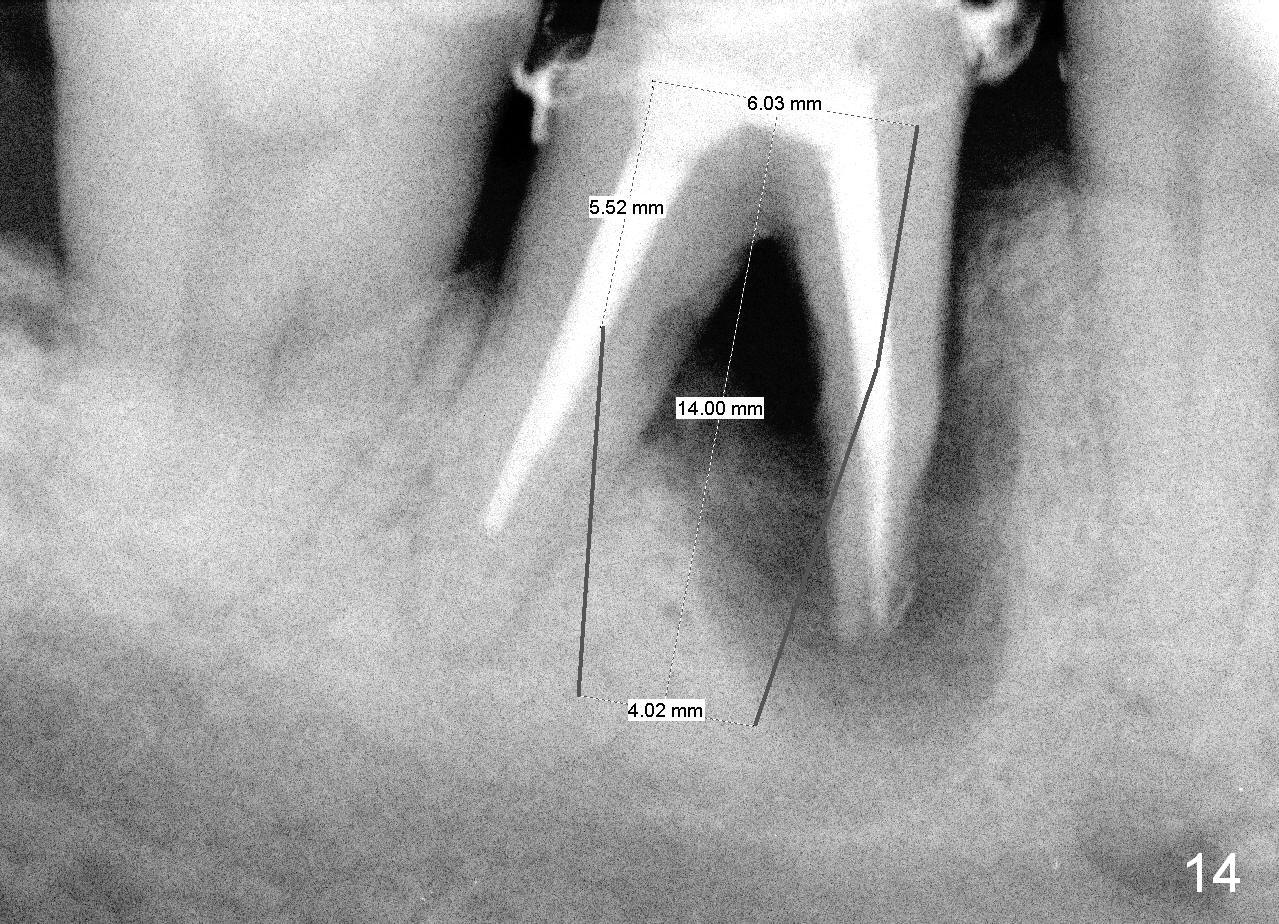

When the perio dressing is removed in office 24 days postop (Fig.9), the rough surface of the implant (R) is exposed buccally. Normally the smooth surface should contact the gingiva (S). Lingually implant/gingiva position is within normal limit (Fig.10). The patient returns for restoration 4 months postop (Fig.11,12). There is bone formation in the mesial socket and new bone appears to have grown toward the implant (Fig.11 <). A straight abutment appears to be in the middle of the edentulous space (Fig.12 A). But it is difficult to seat the crown. Three months post cementation, the patient complains of food impaction mesially (Fig.10 ^), although bone density continues to increase in the mesial socket and there is no mesial coronal thread exposure (*). Retrospectively the implant should be tried to be placed in the septum as much as possible to have a favorable restorative axis (Fig.14). The crown is re-fabricated with larger mesial contact area. It is temporarily cemented because of slightly loose distal contact (Fig.15). A few days later, the patient requests permanent cementation, because although the distal contact is loose, it is easy to remove food. Mesial food impaction is less likely, but it is more difficult to be removed.